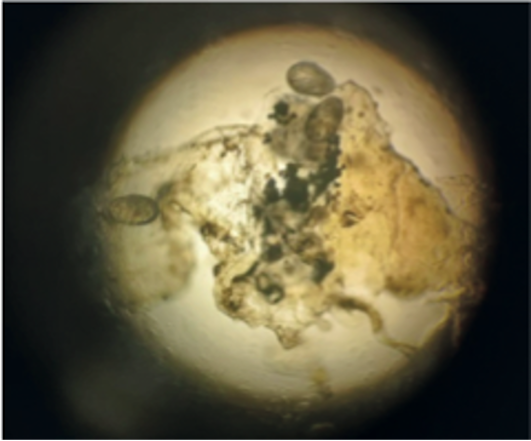

L’emocromo ha mostrato un conteggio dei globuli bianchi di 9.150/μl (con il 20,7% di neutrofili, il 64,6% di linfociti, il 6,9% di monociti, il 7,7% di eosinofili; Hb 8,7 g/dl, MCV 79,2 fl, MCH 28,6 pg, MCHC 36,2 g/dl, reticolociti 4,82% e piastrine 48.500/mm3). È stata avviata una terapia empirica di trattamento topico con permetrina e in considerazione di una parziale risposta clinica è stata somministrato un preparato galenico al 10% di benzil benzoato. La diagnosi clinica della scabbia è stata confermata dall’osservazione dell’acaro attraverso esame microbiologico (Figura 2).